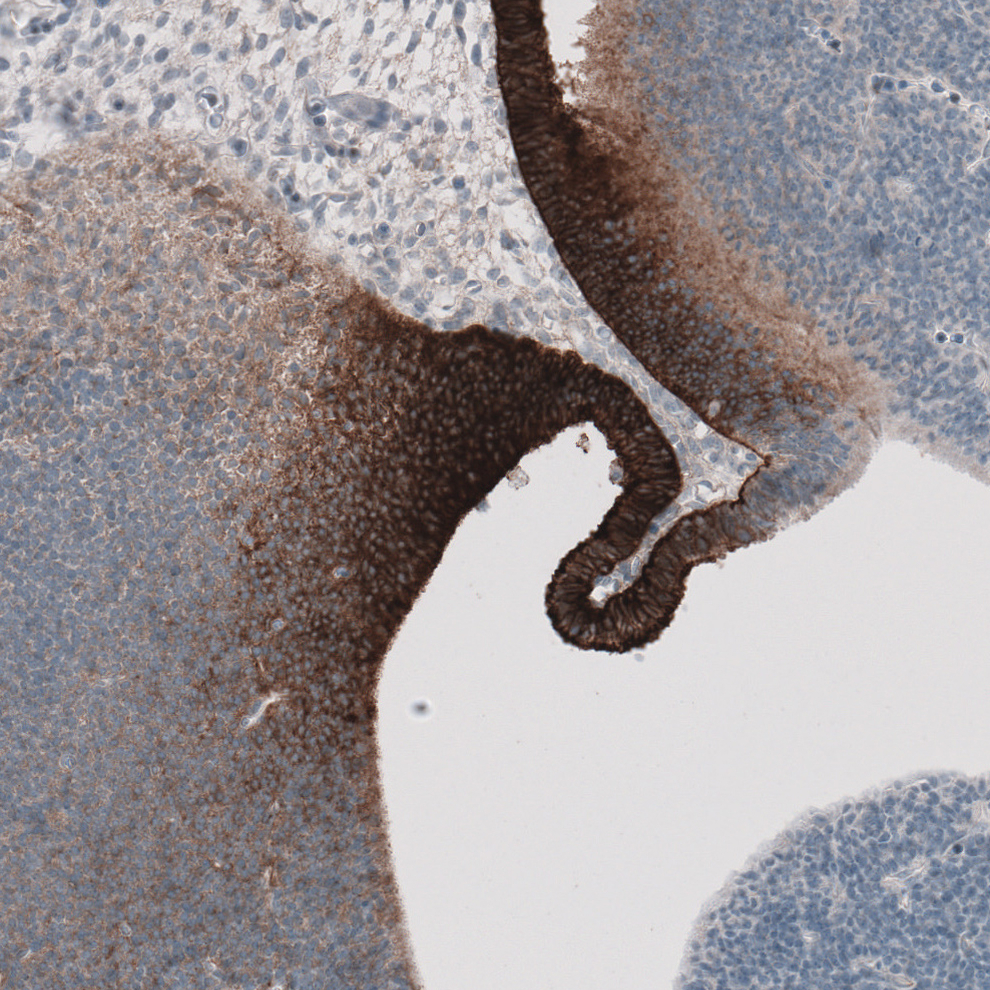

Immunohistochemical staining of human liver shows moderate to strong membranous positivity in hepatocytes.